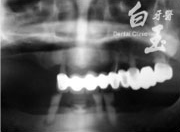

患者全口 X 光

治療前